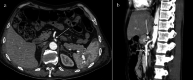

Fig. 12

Power Doppler US and Duplex Doppler US of common iliac veins. a Left common iliac vein (arrow) dilatation in the pre-stenotic tract (14 mm). b Right common iliac vein (long arrow) with regular diameter (12 mm). Right common iliac artery (short arrow). c Duplex Doppler US shows a regular peak speed in the post-stenotic tract of the left common iliac vein (15.8 cm/s) and peak speed reduction in the pre-stenotic tract (7.3 cm/s) -D